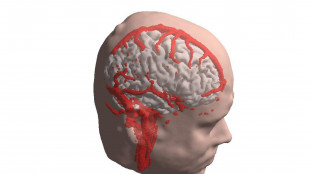

Centro Cuore al Gemelli, cure integrate e hi tech per la cardiologia del futuro

27.000 metri quadrati, 100 posti letto per degenza ordinaria, 28 terapie intensive